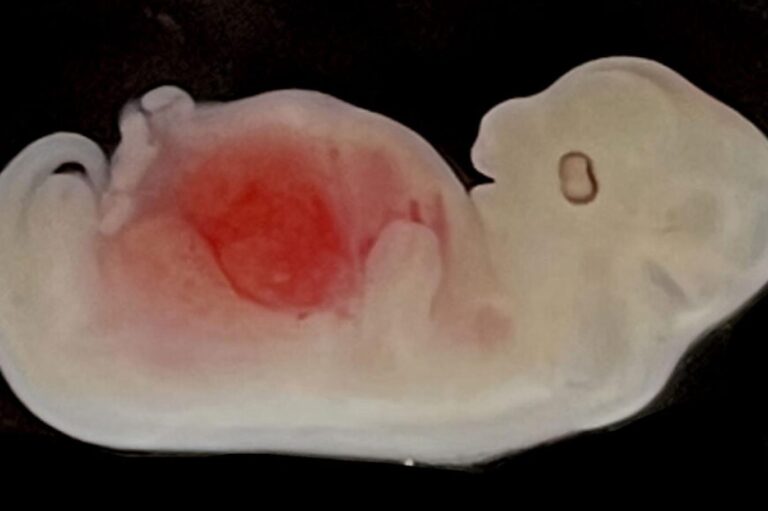

أحد أجنة الخنازير التي زرعت فيها كلى بشرية (ساينس نيوز.أورغ) صحة استزراع كلى بشرية داخل أجنة محتضنة في أرحام بديلة للخنازير by admin 14 سبتمبر، 2023 written by admin 14 سبتمبر، 2023 181 استمر معظمها في النمو بنجاح طوال 28 يوماً اندبندنت عربية \ نيليما مارشال للمرة الأولى، زرع العلماء كلى بشرية داخل أجنة الخنازير تنمو في أرحام بديلة في تلك الحيوانات. وتركت تلك الكلى في تلك الأجنة المختلطة بين البشر والخنازير، كي تنمو طوال 28 يوماً، ما يساوي تقريباً ثلث مدة الحمل في تلك الحيوانات. [تبلغ المدة الكاملة للحمل لدى الخنازير 114 يوماً]. ووجد الباحثون أن الكلى نمت بشكل طبيعي وطورت تركيبتها الطبيعية التي تشمل شبكة من الأنابيب الداخلية الصغيرة، وقد وصلت إلى المرحلة الثانية من نموها حينما استخرجت تلك الأجنة من الأرحام البديلة. ولفت الباحثون إلى أن طرقاً مماثلة قد استخدمت من قبل في تنمية أنسجة بشرية كالدم أو العضلات، إلا أن المحاولات السابقة في زراعة أعضاء بشرية داخل الخنازير لم تنجح. وأعرب ليانغ شيويه لاي، من “معاهد غوانزو للطب الحيوي والصحة” التابع لـ”الأكاديمية الصينية للعلوم”، عن رأي مفاده أن “نهجنا يحسن دمج الخلايا البشرية في الأنسجة المتلقية لها، ويتيح لنا زراعة الأعضاء البشرية في الخنازير”. ولأوقات مديدة، بدا دمج الخلايا الجذعية البشرية [تسمى أيضاً خلايا المنشأ] داخل أجنة الخنازير أشبه بالمستحيل لأن خلايا الخنازير والخلايا البشرية ينتهي بها الأمر إلى التنافس مع بعضها بعضاً. [يشير مصطلح خلايا المنشأ الجذعية إلى الخلايا الأولية التي تظهر بعد مرحلة تلقيح البويضة بحيوان منوي. وخلال مرحلة معينة، يكون معظم الجنين مؤلفاً من تلك الخلايا التي تتفرع منها أنواع الخلايا التي تصنع الأنسجة والأعضاء المختلفة داخل الجسم. ويعني ذلك أن كل خلية منشأ جذعية لديها القابلية على أن تعطي أي نسيج أو عضو في الجسم]. نهجنا يحسن دمج الخلايا البشرية في الأنسجة المتلقية لها، ويتيح لنا زراعة الأعضاء البشرية في الخنازير ولحل تلك المشكلة، استخدم الباحثون تقنية تحرير الجينات لإزالة جينين من أجنة الخنازير، مما أدى إلى تكوين ما يسمى بلغة الوراثة “وضعية” أو “فراغ”، بالتالي تمكن الجنين الذي أزيل منه الجينان، من تقبل الكلى البشرية فاستمرت في النمو داخله. وفي خطوة تالية، أدخل الباحثون تعديلات جينية على الخلايا الجذعية البشرية التي لديها القدرة على التحول إلى أي نوع من الأنسجة في الجسم، بهدف جعلها أكثر قابلية للتطور في داخل جنين الخنزير. وقد نمت تلك الأجنة المؤلفة جزئياً من الخنازير وجزئياً من الإنسان، وتعرف بتسمية “كايمرا”، في المختبر ضمن ظروف تلبي الحاجات المختلفة لخلايا الخنازير والبشر، قبل زرعها في أرحام بديلة داخل إناث الخنازير. [تأتي كلمة كايمرا من المثيولوجيا القديمة وتشير إلى كائنات مؤلفة من أكثر من نوع بيولوجي. وقد جسدت في منحوتات قديمة تظهر مثلاً أسداً برأسين أحدهما لذئب، مع ذيل تنين. وتستعمل علمياً للإشارة إلى ذلك المزيج من الأنواع الحيوانية في جسم واحد]. وفي المجموع، نقل الباحثون 1820 جنيناً إلى أرحام 13 أماً بديلة. وفي خطوة تالية، عمد العلماء إلى إنهاء حمل جميع أمهات الخنازير بعد 28 يوماً لأن المبادئ التوجيهية الأخلاقية [في التجارب البيولوجية] تنصح بعدم ترك كايمرا” إلى اكتمال تطوره تماماً، ثم استخرجت الأجنة بهدف تقييم مدى نجاحها في إنتاج الكلى البشرية. وفي أجنة تراوحت أعمارها ما بين 25 و28 يوماً، وجد العلماء أن الكلى وصلت إلى المرحلة الثانية من التطور، وبدا تركيبها متوافقاً مع بلوغها تلك المرحلة. ووفقاً للباحثين، تطورت الكلى وشكلت الخلايا البشرية 60 في المئة منها، إضافة إلى أن الأجنة احتوت شبكة أنابيب صغيرة مع براعم من الخلايا، ومن شأن تلك التركيبات أن تصبح في النهاية الحالب الذي يربط الكلية بالمثانة. وأشارت التحاليل إلى أن الخلايا البشرية تموضعت في الكلى غالباً، فيما تكون بقية الجنين من خلايا خنازير. وفي تعليق على تلك المعطيات، لفت الخبير في “معاهد غوانزو للطب الحيوي والصحة”، تشن داي، “وجدنا أنه حينما تنشأ وضعية معنية في جنين الخنزير، فستذهب إليها الخلايا البشرية بشكل طبيعي”. وكجزء من الخطوات التالية، يرغب الفريق في إتاحة المجال أمام الكلى [البشرية المستزرعة] بالتطور لفترة أطول، ويعملون على توليد أعضاء بشرية أخرى في الخنازير، بما في ذلك القلب والبنكرياس. ويتمثل هدفهم في نهاية المطاف، باستخدام التكنولوجيا لزراعة الأعضاء البشرية، فيما يرى باحثون أن ثمة أعمالاً كثيرة يجب إنجازها قبل الوصول إلى تلك النقطة. وكذلك أشار ميغيل إستيبان، من “معاهد غوانزو للطب الحيوي والصحة” إلى ملمح آخر في ذلك الإطار، إذ اعتبر أنه “قد نحتاج إلى هندسة الخنازير [إدخال تعديلات وراثية جينية عليها] بطريقة أكثر تعقيداً. وهذا يجلب معه أيضاً بعض التحديات الإضافية. ومن ثم، قبل أن نصل إلى تلك الحالة المتقدمة في صنع أعضاء وإتاحتها أمام الممارسة السريرية، توفر هذه الطريقة نافذة لدراسة مسار تكون الجسم البشري”. وأردف، “يمكننا تتبع الخلايا البشرية التي نحقنها، إضافة إلى التلاعب في جيناتها، كي نتمكن من دراسة الأمراض وكيفية تكوين الأنواع المختلفة من الخلايا”. ونشر هذا البحث في المجلة العلمية المتخصصة بخلايا المنشأ الجذعية “سيل ستيم سيل” Cell Stem Cell. وتعليقاً على البحث، ذكر دوسكو إيليتش، أستاذ علوم الخلايا الجذعية في “كينغز كوليج لندن” King’s College London “تصف الورقة خطوات رائدة في نهج جديد للهندسة الحيوية للأعضاء باستخدام الخنازير كحاضنات لزراعة الأعضاء البشرية وزراعتها. وبحسب المؤلفين، هنالك تحديات كثيرة. هل سيثبت هذا النهج أنه الحل النهائي؟ الوقت وحده يتكفل بإعطاء الإجابة”. وأضاف “على رغم ذلك، تحتاج هذه الاستراتيجية الآسرة إلى مزيد من الاستكشاف”. وفي نفس مماثل، صرح مؤسس “المنظمة الوطنية لزراعة الأعضاء في إسبانيا”، رافائيل ماتيسانز، أن “الخطوات التالية ستتمثل بالسماح للأجنة بالنمو لفترة أطول، ثم الشروع في فعل الشيء نفسه مع الأعضاء والأنسجة الأخرى، على رغم أن الكلى هي بلا شك أكثر الأعضاء المطلوبة في عمليات زرع الأعضاء”. وبرأي ماتيسانز، “يعترف المؤلفون أنفسهم بأن الاستخدام السريري لهذه التكنولوجيا لا يزال على بعد سنوات، ولكن الدراسة هي إنجاز بارز على طريق الإنتاج الواسع للأعضاء القابلة للزرع”. © The Independent المزيد عن: كلى بشريةأجنة خنازيرأرحام بديلةأعضاء بديلة 0 comment 0 FacebookTwitterPinterestEmail admin previous post دعوات في بريطانيا لتوفير لقاح كورونا للجميع وسط قلق حيال متحورة جديدة next post لدينا حاستان سادسة وسابعة ويمكن أن نعزز قدراتهما You may also like أعراض السرطان الصامتة: علامات خفية قد تكون قاتلة 28 أبريل، 2026 اختراق طبي: الذكاء الاصطناعي يكشف ألزهايمر بدقة غير... 11 مارس، 2026 طرق بسيطة لتخفيف أعراض التهاب المفاصل 11 مارس، 2026 سرطان الرئة الأكثر فتكا… والكشف المبكر ينقذ الآلاف 7 مارس، 2026 فتيات يقعن في فخ PPD مع موسم الحناء... 7 مارس، 2026 مفاجأة علاجية… عقار قديم يُظهِر فائدة جديدة للذاكرة 5 مارس، 2026 مسنون يقاومون الخرف: ما سر ذاكرتهم الخارقة؟ 4 مارس، 2026 تغييرات طفيفة في نمط الحياة تقلل من خطر... 26 فبراير، 2026 مارسه صباحاً ومساءً… نشاط يومي قد يبطئ السرطان 24 فبراير، 2026 (7 تغيرات) في الشخصية في منتصف العمر قد... 24 فبراير، 2026